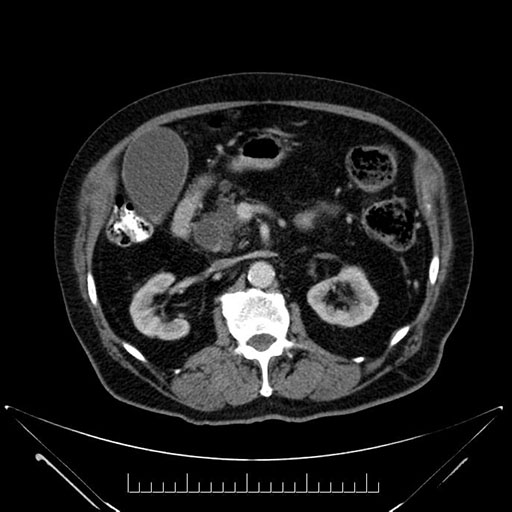

Whipple (pancreaticoduodenectomy) [case 7]

Imaging Analysis

Look through the patient's CT scan to identify any areas of concern for the necessary procedure.

Axial - 3 months prior